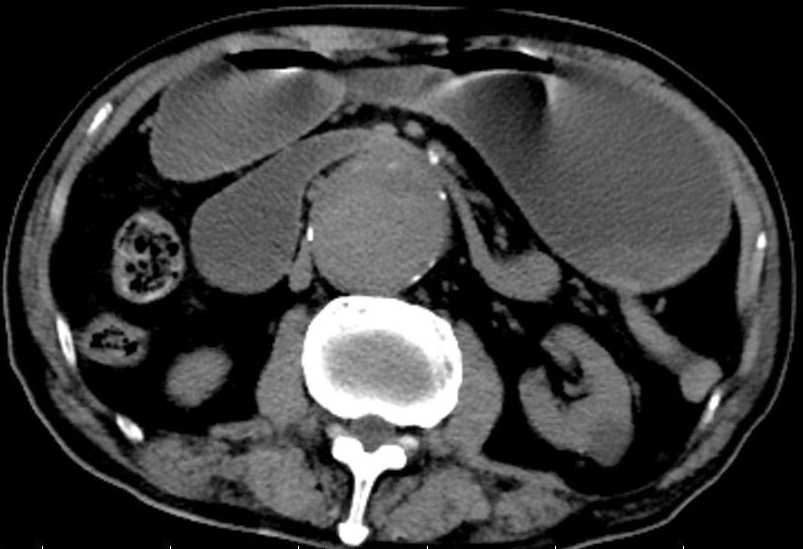

An 89-year-old man with a past medical history significant for hypertension, coronary heart disease, diabetes mellitus and renal dysfunction presented with a chief complaint of nausea, vomiting and abdominal discomfort for 3 weeks. Abdominal examination was unremarkable, apart from a pulsatile mass in the central abdomen. The laboratory findings included elevation of inflammatory parameters, increased creatinine and electrolyte disturbances. Abdominal computed tomography revealed a 5.7 cm abdominal aortic aneurysm with obstruction at the horizontal portion of the duodenum and upstream dilatation (Figure 1A). Meanwhile, computed tomography angiography led to a further exclusion of Wilkie syndrome, which has interesting correlations and differences as causes of extrinsic duodenal compression. He was subsequently diagnosed with aortoduodenal syndrome. Even if surgical management is the preferred treatment option, he was managed with medication and gastrointestinal decompression in overall consideration of his general conditions. After the symptoms improved, the patient was discharged and followed up as an outpatient. Aortoduodenal syndrome is an extremely rare entity, with only about 50 cases reported in the literature, since William Osler described the aortoduodenal syndrome in 1905 firstly [1]. Different from occuring in young women with a thin body habitus in Wilkie syndrome, aortoduodenal syndrome is ubiquitous in aging men. Moreover, we can find a decrease in mesenteric fat tissue and the aortomesenteric angle (to below 25°) is showed in the imaging of the Wilkie syndrome other than aortoduodenal syndrome. As for treatment, even if surgical resection is the treatment of ultimate choice for this disease, some argue that conservative therapy should still be the preferred course of action, as it may help to reduce adverse effects of the initial insult for whom suffered with the aneurysmal rupture [2].

Figure 1: Abdominal computed tomography revealed a 5.7 cm abdominal aortic aneurysm with obstruction at the horizontal portion of the duodenum and upstream dilatation.